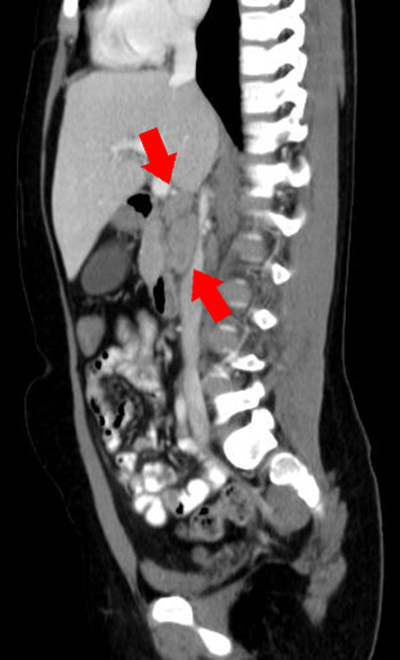

Valorizzando il dato anamnestico dei dolori addominali con febbre, seppur alla luce di una ecografia addome negativa, nel sospetto di una possibile raccolta ascessuale profonda abbiamo eseguito la TAC dell'addome con evidenza di una formazione ovoidale localizzata tra la vena cava superiore e la terza porzione duodenale a margine netti, con aspetto non colliquato, e la presenza di altre piccole formazioni ovoidali, reattive di diametro di circa 2 cm di diametro (Figura 1 e Figura 2).

Figura 1 e Figura 2. Formazione ovoidale solida a maggior diametro cranio-caudale di circa 4x3x2 cm tra vena cava superiore e terza porzione duodenale a margini netti, di aspetto non colliquato con presenza di altre formazioni ovoidali pi� piccole, reattive il maggiore di 2 cm di diametro.